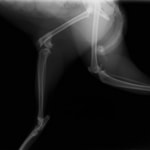

ペルシャ猫 11ヶ月齢 雄

他院にて左大腿骨遠位の成長板骨折(salter-harrisⅠ型)が認められており、治療相談を目的として来院。当院にて、キルシュナーワイヤーを用いたピンニングにより骨折部位の整復を行いました。術後の経過は良好で、現在も経過観察中です。

術前レントゲン